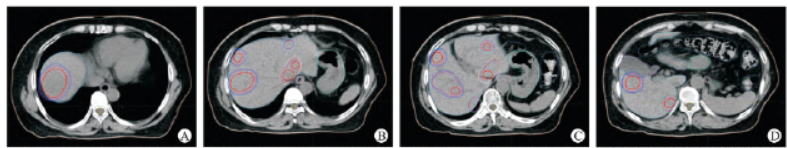

患者经碳离子治疗后的临床表现如下:①患者治疗结束后首次复查腹部MRI 提示肝脏病灶较前缩小,根据RECIST1.1 实体肿瘤疗效评价标准,疗效评价为部分缓解(partial remission,PR)(图4),下阶段将继续完成1、3、5 年的随访;②患者治疗结束后4 个月复查腹部MR 提示肝S8 段病灶较前明显缩小,大小约2.2 cm × 2.0 cm × 1.0 cm,DWI示弥散受限,ADC 值1.534 mm3 /s,其余病灶显示不明确,根据RECIST1.1 实体肿瘤疗效评价标准,疗效评价为PR(图5);③治疗前后临床各项指标比较,治疗后0.5 个月及4 个月复查时,肿瘤长径、SER、AFP 逐渐降低,而ADC 值不断升高,疗效评价均为PR,本院检查见表1。

图4 CIRT 治疗后首次(2023 - 04 - 03)MRI 复查A - G:对比增强MRI T 增强肝内病灶较前明显变小,部分显示欠清,较大者位于肝S8 段,大小约3.2 cm × 2.8 cm × 2.2 cm;H - I:DWI 示弥散受限,ADC 值1.188 mm3 /s。

图5 治疗后4 个月第二次复查MRIA - I:肝脏大部分病灶消失,较大病灶明显缩小,无皮肤急性不良事件,且无3 级RTOG 急性效应。